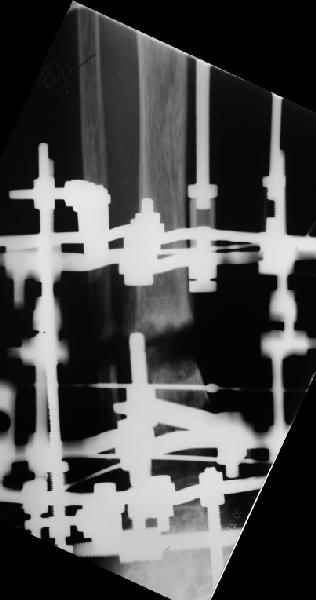

I played with your image using some orthopedic software we have been developing for digital

image analysis.

What you see marked up is the intercept of two mid-line tool centre lines, used to define the CORA. An angle tool gives the angular deformity and a circle tool is applied to show that a correction around the CORA through the old # will restore alignment without much translation.